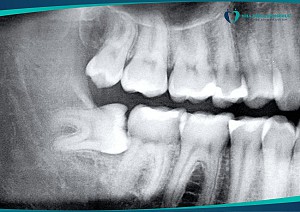

Theo quan niệm thường thấy ở bệnh nhân đó là răng khôn mọc thẳng dễ nhổ và sẽ mất ít thời gian hơn, điều này chỉ đúng một phần. Đánh giá mức độ khó của răng khôn, ngoài hướng mọc ra còn phụ thuộc vào các yếu tố: chiều cao của hàm dưới, góc nghiêng so với răng số 7, hình thể chân răng, hướng thoát của răng, độ tuổi, các cấu trúc giải phẫu liên quan…

Vì vậy, việc thăm khám cũng như chụp phim là vô cùng quan trọng để có cái nhìn ban đầu về răng khôn cũng như mức độ khó của nó.

Bước 2: Chụp phim X-quang 2 chiều hay 3 chiều. Chỉ định chụp phim 3 chiều trong nhổ răng khôn để đánh giá chi tiết mối liên quan của răng khôn với các cấu trúc giải phẫu cũng như đánh giá tốt hơn hình thể chân răng, loại phim này đang dần trở nên thông dụng khi bắt đầu bất kì một tiểu phẫu nhổ răng khôn nào.